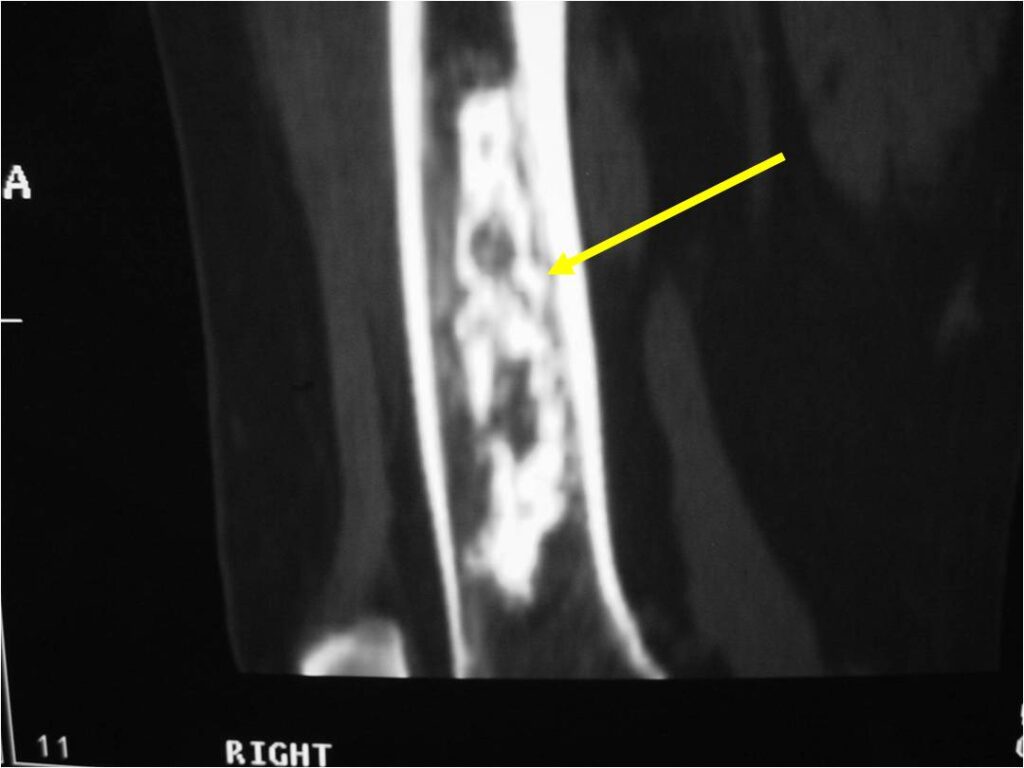

- MRI

- Lobulated margin

- Marked increased intensity long TR images

- Calcified chondroid – low intensity all sequences

MRI:

- Lobulated margin (Lobular Growth Pattern)

- T1 Weighted Images: Intermediate Signal Intensity

- Calcifications will be low signal

- T2 Weighted Images: High Signal Intensity

- High water content shows as high signal on T2 weighted images

- There should never be any cortical destruction nor a soft tissue component. If this exists then the tumor must be a chondrosarcoma.

- Endosteal scalloping and cortical expansion is acceptable for phalangeal tumors. In most benign long bone cartilage tumors there is minimal endosteal scalloping but there should be no cortical expansion nor thickening. There should be no cortical destruction and no soft tissue component associated with an enchondroma. Cortical destruction, periosteal thickening, cortical expansion and a soft tissue component indicates a chondrosarcoma of the long bone.

- Endosteal erosion>2/3 cortical thickness on a CT scan